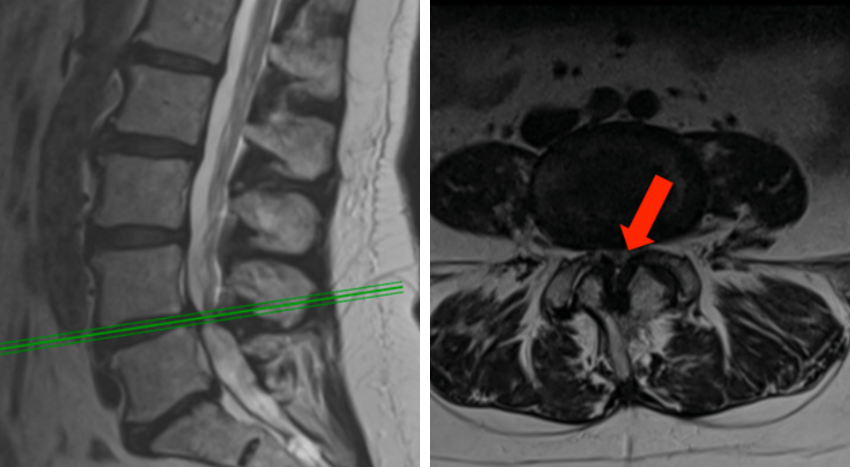

MRI(자기공명영상): 척추관 내 신경의 압박 여부, 협착 정도 평가에 가장 유용한 검사다.